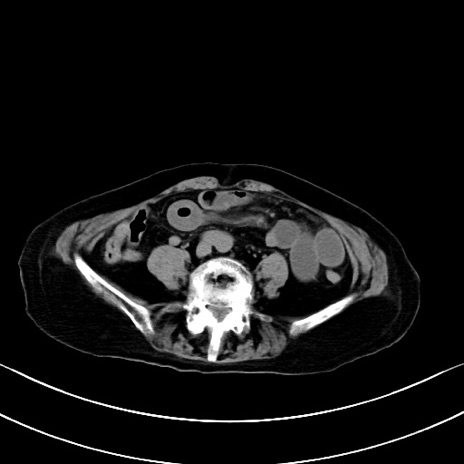

横断像

他院CT